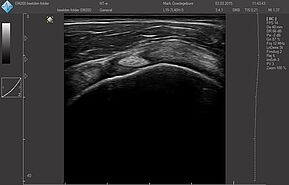

Области исследований:

- Брюшная полость

- Акушерство и гинекология

- Урология

- Щитовидная железа

- Молочная железа

- Кардиология

- Костно-мышечная система

- Педиатрия

- Нейросонография

- Исследование сосудов

- Транскраниальные исследования

Датчики имеют большую чувствительность и высокое разрешение, благодаря чему обеспечивают максимальное проникновение и улучшают соотношение сигнал /шум. В результате формируется максимально четкая детализированная картинка УЗИ изображения.